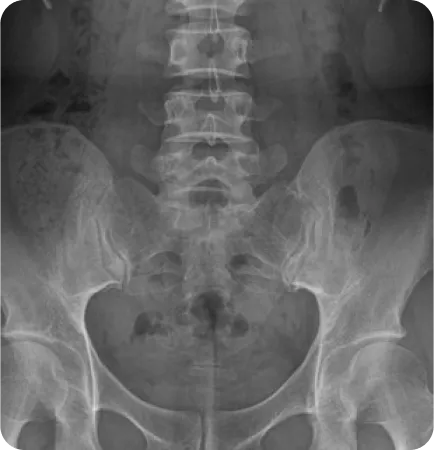

골반 틀어짐 유형별 치료

유형 이미지 특징 치료법

틀어진 골반

(업슬립)

짝궁둥이 체형, 종아리에 비해

허벅지가 두껍고 골반높이 차이가

심한 경우

• 실제 다리길이 차이가 있는지 확인

• 맞춤깔창 처방

• 정골추나요법, 골반 도수 동시 시행

• 중둔근 강화 및 대퇴근막장근 이완기법

벌어진 골반

엉덩이가 유달리 넓고 허벅지가 퍼진 경우

팔자걸음 유형

• 허벅지 안쪽, 골반 내측 근육을 강화하고, 엉덩이 뒤쪽 근육을 이완하는 도수치료

• 골반을 뒤에서 앞으로 교정하는 정골추나기법

좁아진 골반

허벅지가 두껍고 엉덩이 근육의 볼륨이

약한 안짱 걸음 유형

• 약한 엉덩이 뒤쪽 근육을 강화하며 복부, 허벅지 안쪽 근육을 이완하는 도수치료

• 골반을 앞에서 뒤로 교정하는 정골추나기법

앞으로 기운 골반

(골반 전방경사)

오리 궁둥이 타입으로

골반이 앞으로 기울어져 아랫배가 나오고

허리가 앞으로 휘어서

바로 누워 자기 힘든 유형

• 허벅지 앞쪽과 허리 근육을 이완하고 복근과 엉덩이 근육을 강화하는 도수치료

• 천골 및 장골변위를 교정하는 추나요법

• 평발인 경우 맞춤깔창 처방

뒤로 기운 골반

(골반 후방 경사)

골반이 뒤로 기울어져 허리가 편평하며

허벅지 뒤쪽 근육이 많이 짧아진 유형

• 허벅지 뒤쪽 근육과 복근을 이완하고 허리근육과 허벅지 앞쪽 근육을 강화하는 도수치료

• 천골과 장골 변위를 교정하는 추나요법

• 요족인 경우 맞춤깔창 처방